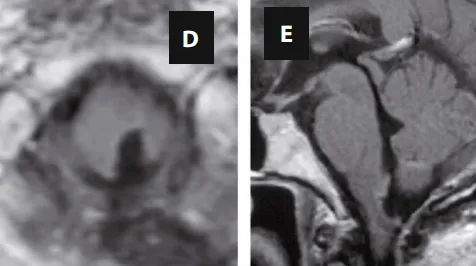

术后MRI

面对这个位于手术“禁区”的复杂病变,INC的巴特朗菲教授为安妮制定了精密的手术方案。他主刀施行了后正中入路肿瘤切除术,并在持续术中神经电生理监测的全程护航下,精准操作,顺利切除了肿瘤,解决了安妮打嗝的这一罪魁祸首。术后影像证实了肿瘤的满意切除。